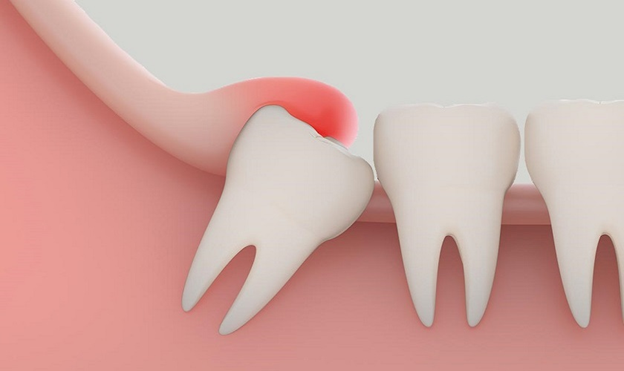

- Răng khôn mọc kẹt

- Cung hàm không đủ khoảng trống, chỉ một phần thân răng mọc lên.

- Thường gây sưng, đau, viêm nướu hoặc lợi trùm.